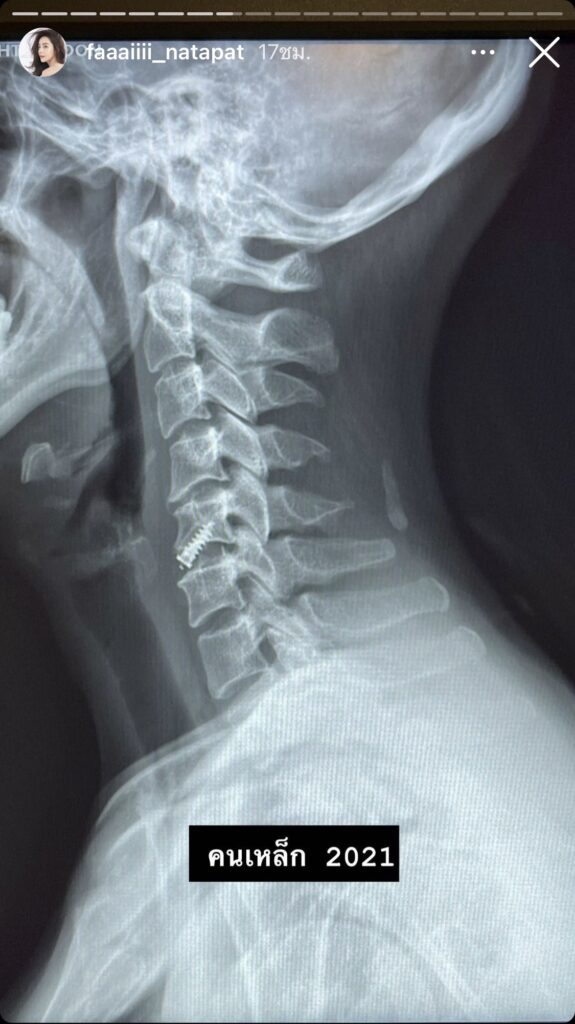

ทำเอาหลายคนตกใจ และอดเป็นห่วงไม่ได้ เมื่อสาวปุยฝ้าย – ณัฎฐพัชร์ วิภัทรเดช หรือปุยฝ้าย เอเอฟ โพสต์ภาพขณะเข้ารักษาตัวที่โรงพยาบาล พร้อมกับแจ้งข่าวว่ากับทุกคนว่าที่ตอนนี้เธอไม่ได้รับสายโทรศัพท์จากใคร เพราะพูดไม่สะดวก เนื่องจากป่วยเป็นหมอนอรองกระดูกทับเส้นประสามมานานกว่า 2 ปี ทำให้มีอาการชาและกล้ามเนื้ออ่อนแรง ประกอบกับไม่นานมานี้เธอตกบันได หัวฟาดช้ำ เลยทำให้อาการทรุดลง กล้ามเนื้ออ่อนแรง เขียนหนังสือไม่ได้ หมอจึงพิจารณาแล้วว่ารอช้าไม่ได้ อาจจะทำให้อาการแย่ไปมากกว่านี้ จึงได้ทำการผ่าตัดรักษาเป็นที่เรียบร้อยแล้ว พร้อมขอบคุณทุกๆคนที่แสดงความห่วงใยและส่งกำลังใจมาให้

“วันนี้มาอัพเดตอาการค่า เพราะมีหลายๆท่านสงสัยว่าฝ้ายเป็นอะไร ไม่ได้รับสายหรือตอบพี่ๆนักข่าวเลยเนื่องจากยังพูดไม่สะดวกนะคะ ฝ้ายเป็นหมอนรองกระดูกทับเส้นประสาทมาสองปีกว่าๆแล้วค่ะ ทำให้มีอาการชาและกล้ามเนื้ออ่อนแรง ที่ผ่านมาพยายามดูแลตัวเองและระมัดระวังในการใช้ชีวิตมาตลอด มีบ้างที่ลืมตัวเวลาทำงานค่ะ🤣แต่เนื่องจากก่อนหน้านี้ไม่นานฝ้ายตกบันได ศรีษะฟาดซ้ำไปอีก เลยทำให้อาการทรุดลง กล้ามเนื้ออ่อนแรง เขียนหนังสือก็ไม่ได้ คุณหมอพิจารณาแล้วว่าไม่ได้แล้ว ไม่อย่างนั้นจะแย่กว่านี้ เลยได้ทำการผ่าตัดรักษาให้ฝ้ายเรียบร้อยค่ะ กราบขอบพระคุณ คุณหมอวิชาญ ยิ่งศักดิ์มงคล ที่น่ารักกับฝ้ายอย่างที่สุด และทีมแพทย์ร่วมผ่าตัดอีก 3 ท่าน พี่นก พี่แหม่ม ที่คอยดูแลตลอด รวมถึงพี่ๆพยาบาล ของ รพ. BNH ด้วยนะคะ และครอบครัวสุดที่รัก แม่ พี่ตาม นอร์จ เพื่อนๆพี่ๆทุกคน ที่เป็นห่วงฝ้ายนะคะ^^ #สุขภาพดีคือดีที่สุด #จ่ายเงินเองประกันไม่เกี่ยว🤣”